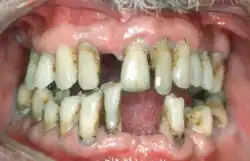

Person with periodontitis

There were several attempts to introduce an agreed-upon classification system for periodontal diseases: in 1989, 1993, 1999,[67] and 2017.